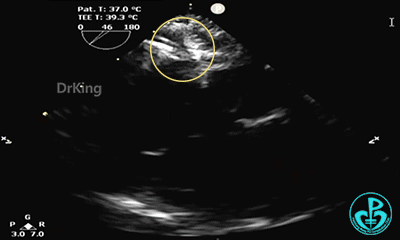

完全释放后超声下观察

主动脉短轴切面显示封堵器呈Y字型抱住主动脉根部,夹持稳定。

封堵器形态良好,未见分流,封堵成功。